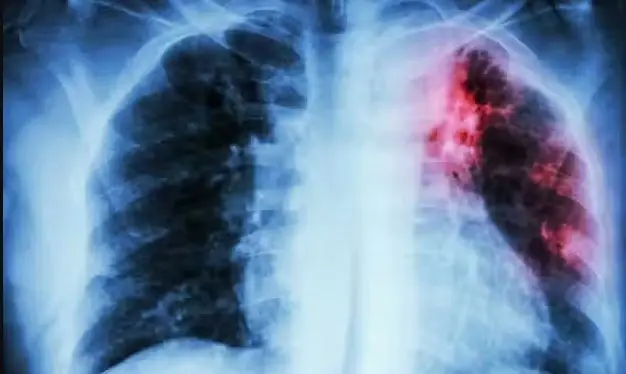

El Minsa también puso en marcha en abril pasado un programa de capacitación a profesionales del sector para poder detectar la tuberculosis mediante rayos X con inteligencia artificial (IA).

Perú es uno de los países con mayor cantidad de casos de tuberculosis en Latinoamérica, pues cada año se diagnostican alrededor de 27.000 nuevos contagios de esta enfermedad infecciosa, y 17.000 de tuberculosis pulmonar frotis positivo, según cifras oficiales. EFE